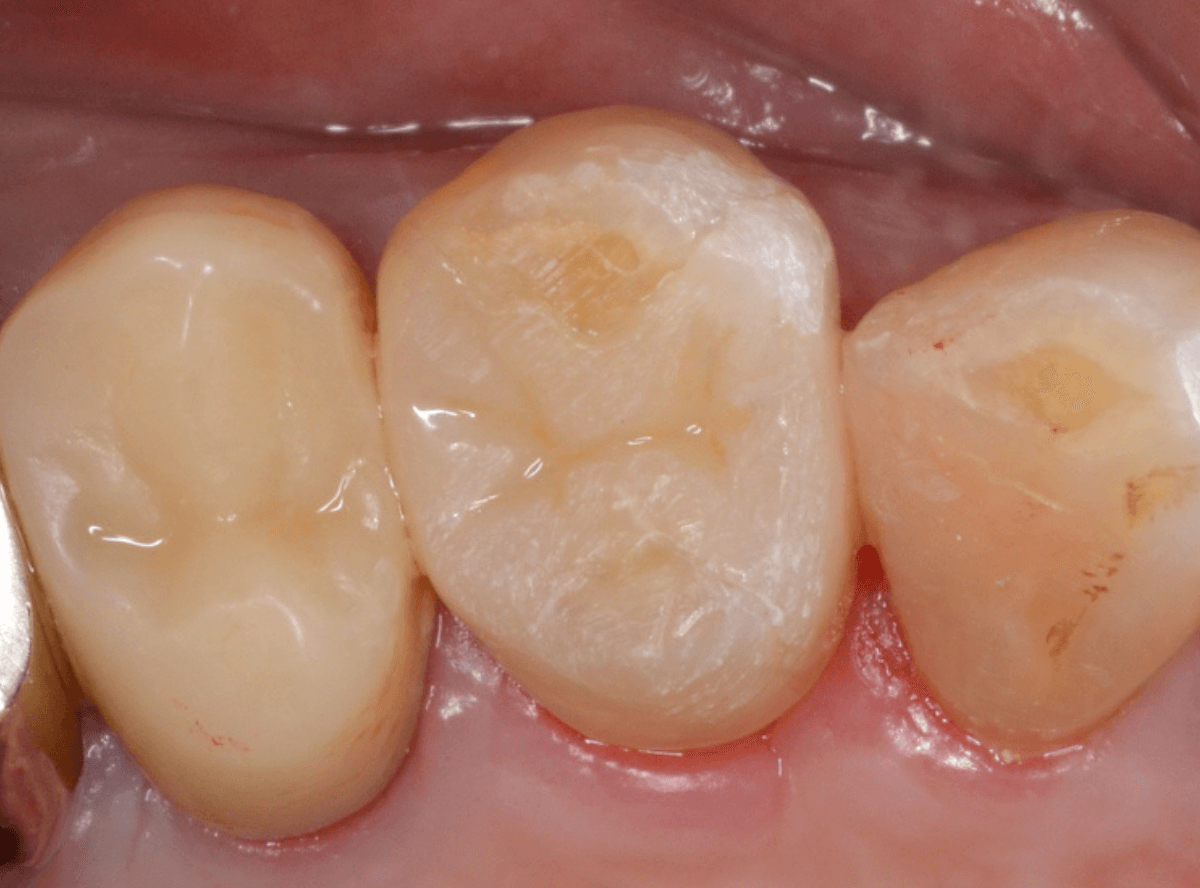

set後の写真です。

患者さんにも満足していただける仕上がりになりました。

治療前後の比較写真になります。